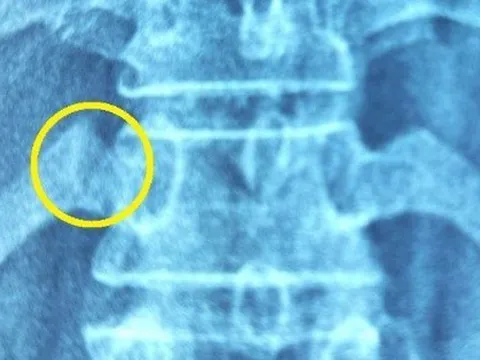

Bị gãy xương sườn vì đi bấm huyệt, bẻ khớp

Người đàn ông tham gia tiệc tùng và uống nhiều rượu bia, bị rối loạn tiêu hóa nên nhập viện. Sau đó bệnh nhân thấy mệt mỏi và đau lưng nên đi bấm huyệt và bẻ khớp thì bị gãy xương sườn.